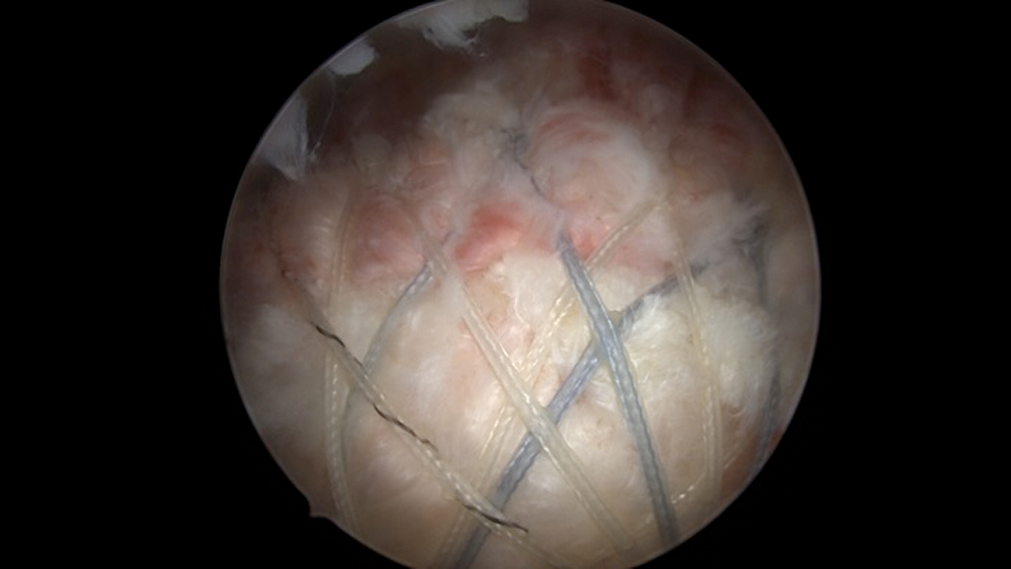

Transosseous-Equivalent Double-Row Repair

Double-row transosseous-equivalent repairs were performed by placing 2 metal 5.5-mm corkscrew suture anchors (Arthrex) loaded with two No. 2 FiberWire sutures (Arthrex). Suture anchors were placed at the anatomic neck of the greater tuberosity, 1 anterior and 1 posterior, separated by at least 1 cm. Sutures were passed in a horizontal mattress fashion a few millimeters lateral to the musculotendinous junction in the posterosuperior rotator cuff. All stitches were then tied. Four tails of these previously tied sutures were then brought over to a 5.5-mm BioComposite SwiveLock anchor (Arthrex) placed at least 1 cm distal to the tip of the greater tuberosity just posterior to the biceps groove. The sutures were tensioned, and the anchor was inserted. Remaining tails were brought over to another 5.5-mm BioComposite SwiveLock anchor (Arthrex) placed at least 1.5 cm posterior to the first anchor. The sutures were tensioned, and the anchor was inserted (Figures 1 and 2).

Full-thickness supraspinatus tear viewed from the posterior portal.

Arthroscopic transosseous-equivalent rotator cuff repair.